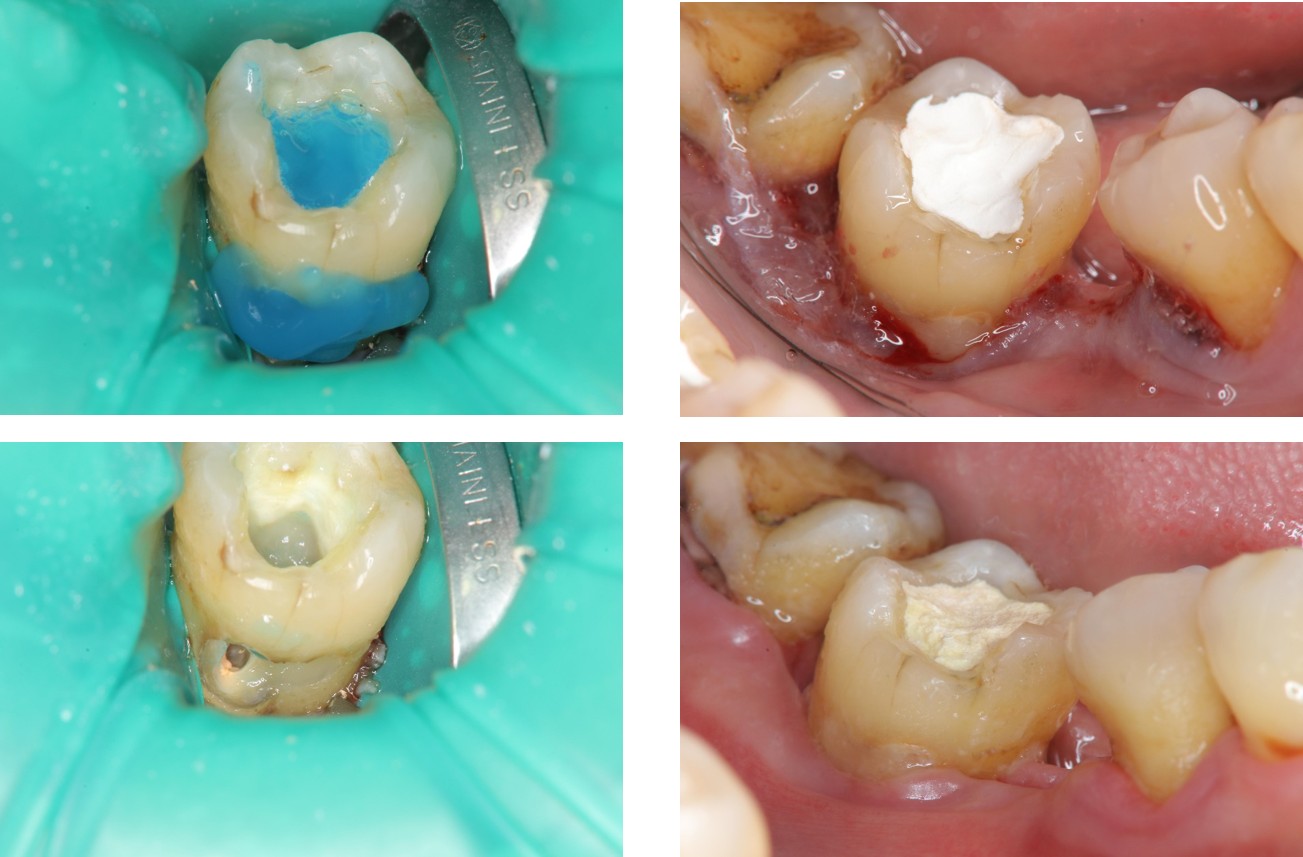

水雷射牙冠增長手術及樹脂復形

陶瓷冠塊體製備

使用橡皮障隔離並黏著

治療後,功能與美觀恢復

深度牙齦下蛀牙,可以使用雷射牙冠增長手術,將蛀牙的齒質移除,並進一步以複合樹脂填補。